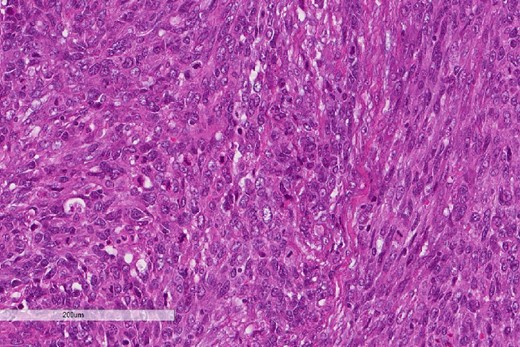

A review of the previously resected esophageal tumor revealed the presence of both epithelial and sarcomatous components. The epithelial component was composed of moderately to poorly differentiated adenocarcinoma, while the sarcomatous component showed hyperchromatic round to spindle cells with scant cytoplasm and frequent mitoses (Figs 3–6). The intrathoracic tumor showed a similar morphology as the sarcomatous component of the esophageal tumor, with focal rhabdomyoblastic differentiation (Fig. 7). The latter was strongly positive for desmin, myogenin, and MyoD1 and was focally positive for synoplastin, CD56, CD 10, and FL1.

High power magnification of the esophageal tumor showing the adenocarcinoma intermixed with spindle cell sarcoma.